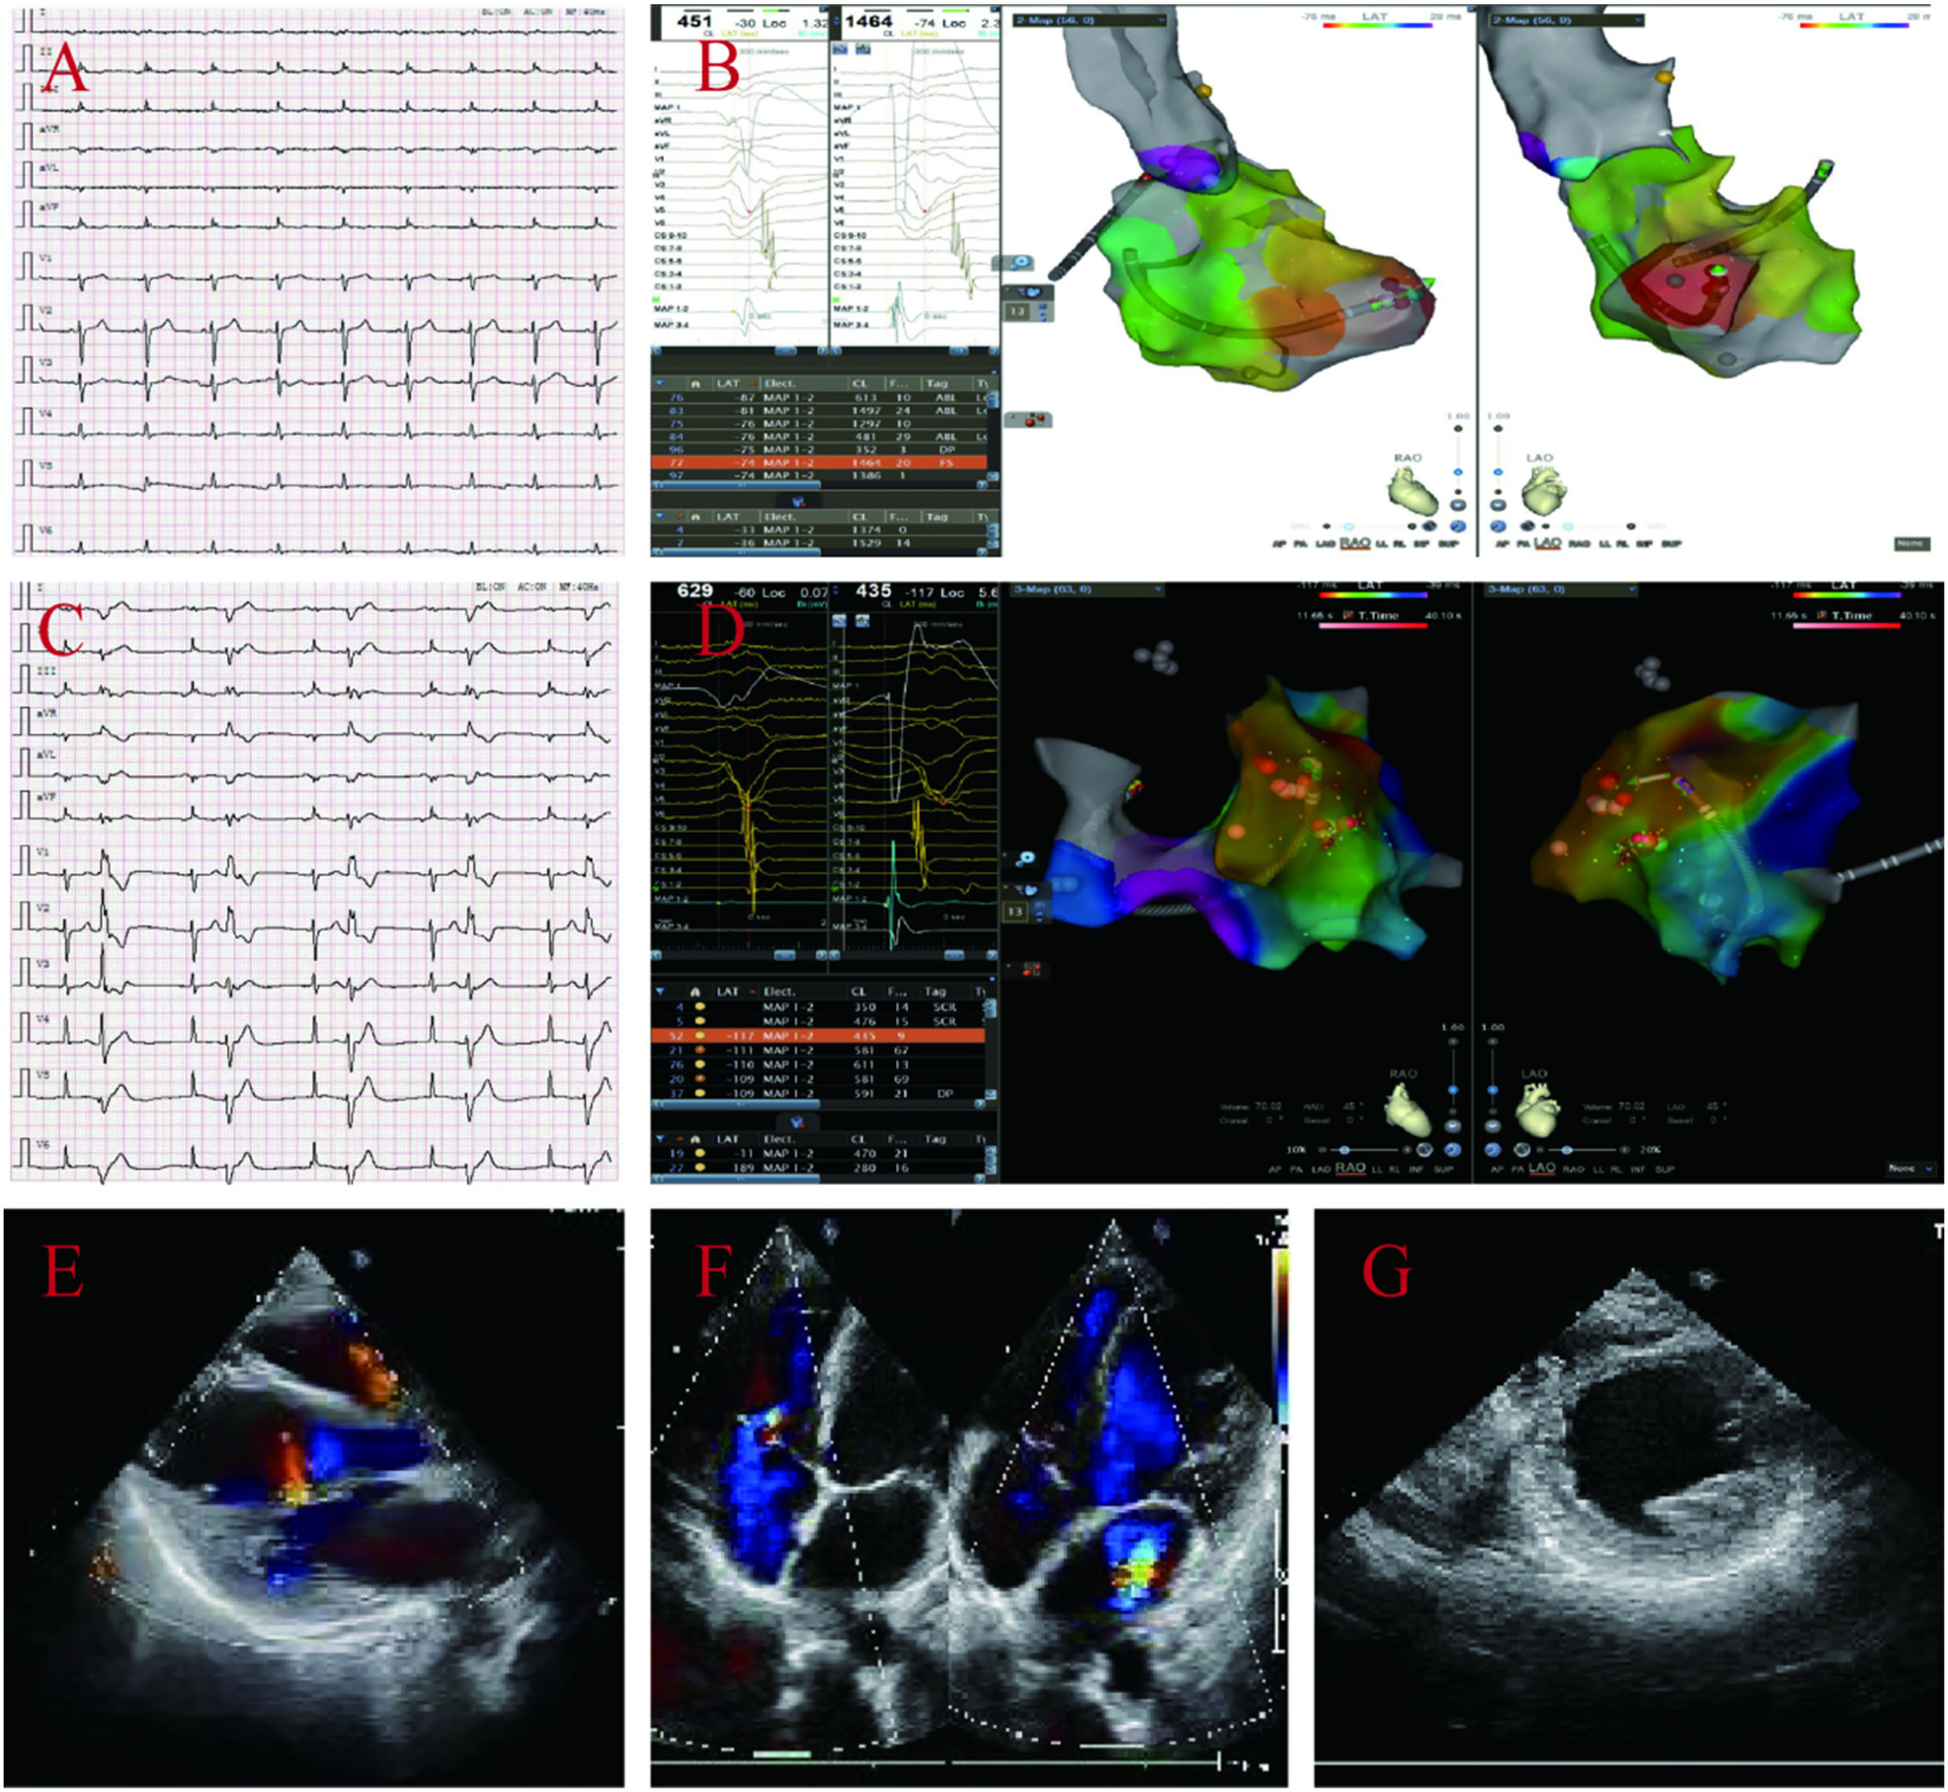

The proband's daughter A (39 years old) also presented with multiple syncope symptoms, and electrocardiogram and electrophysiology revealed frequent multifocal ventricular premature beats and low voltage in limb leads; echocardiography revealed left atrial ventricular enlargement, global weakening of wall motion, decreased left ventricular systolic and diastolic function, and no abnormalities in the right atrium and ventricle (Figures 3A–G); multiple attempts to perform MRI for her failed to complete the examination because she developed claustrophobic syndrome manifestations such as fear, tachycardia, and increased respiration during the examination. Genetic testing revealed that she carried two rare mutations: the heterozygous variant c.8187delC (p.Gln2730SerfsTer16) in the DSP gene(suspected causative), and the heterozygous missense variant c.5351A > G (p.His1784Arg) in the AKAP9 gene (unknown significance)(Supplementary Material S3) which was diagnosed as ALVC based on the above examination results, and comprehensive treatment, such as radiofrequency ablation and drugs, was given.

Figure 3

ECG and electrophysiological of the proband's daughter A display: frequent multi-source ventricular premature beats, low limb lead voltage (A–D). Echocardiography: enlarged left atrial ventricle, overall weakened ventricular wall motion, reduced left ventricular systolic and diastolic function, and no abnormalities in the right atrium and ventricle, left ventricular EF44% and FS22% (E–G).